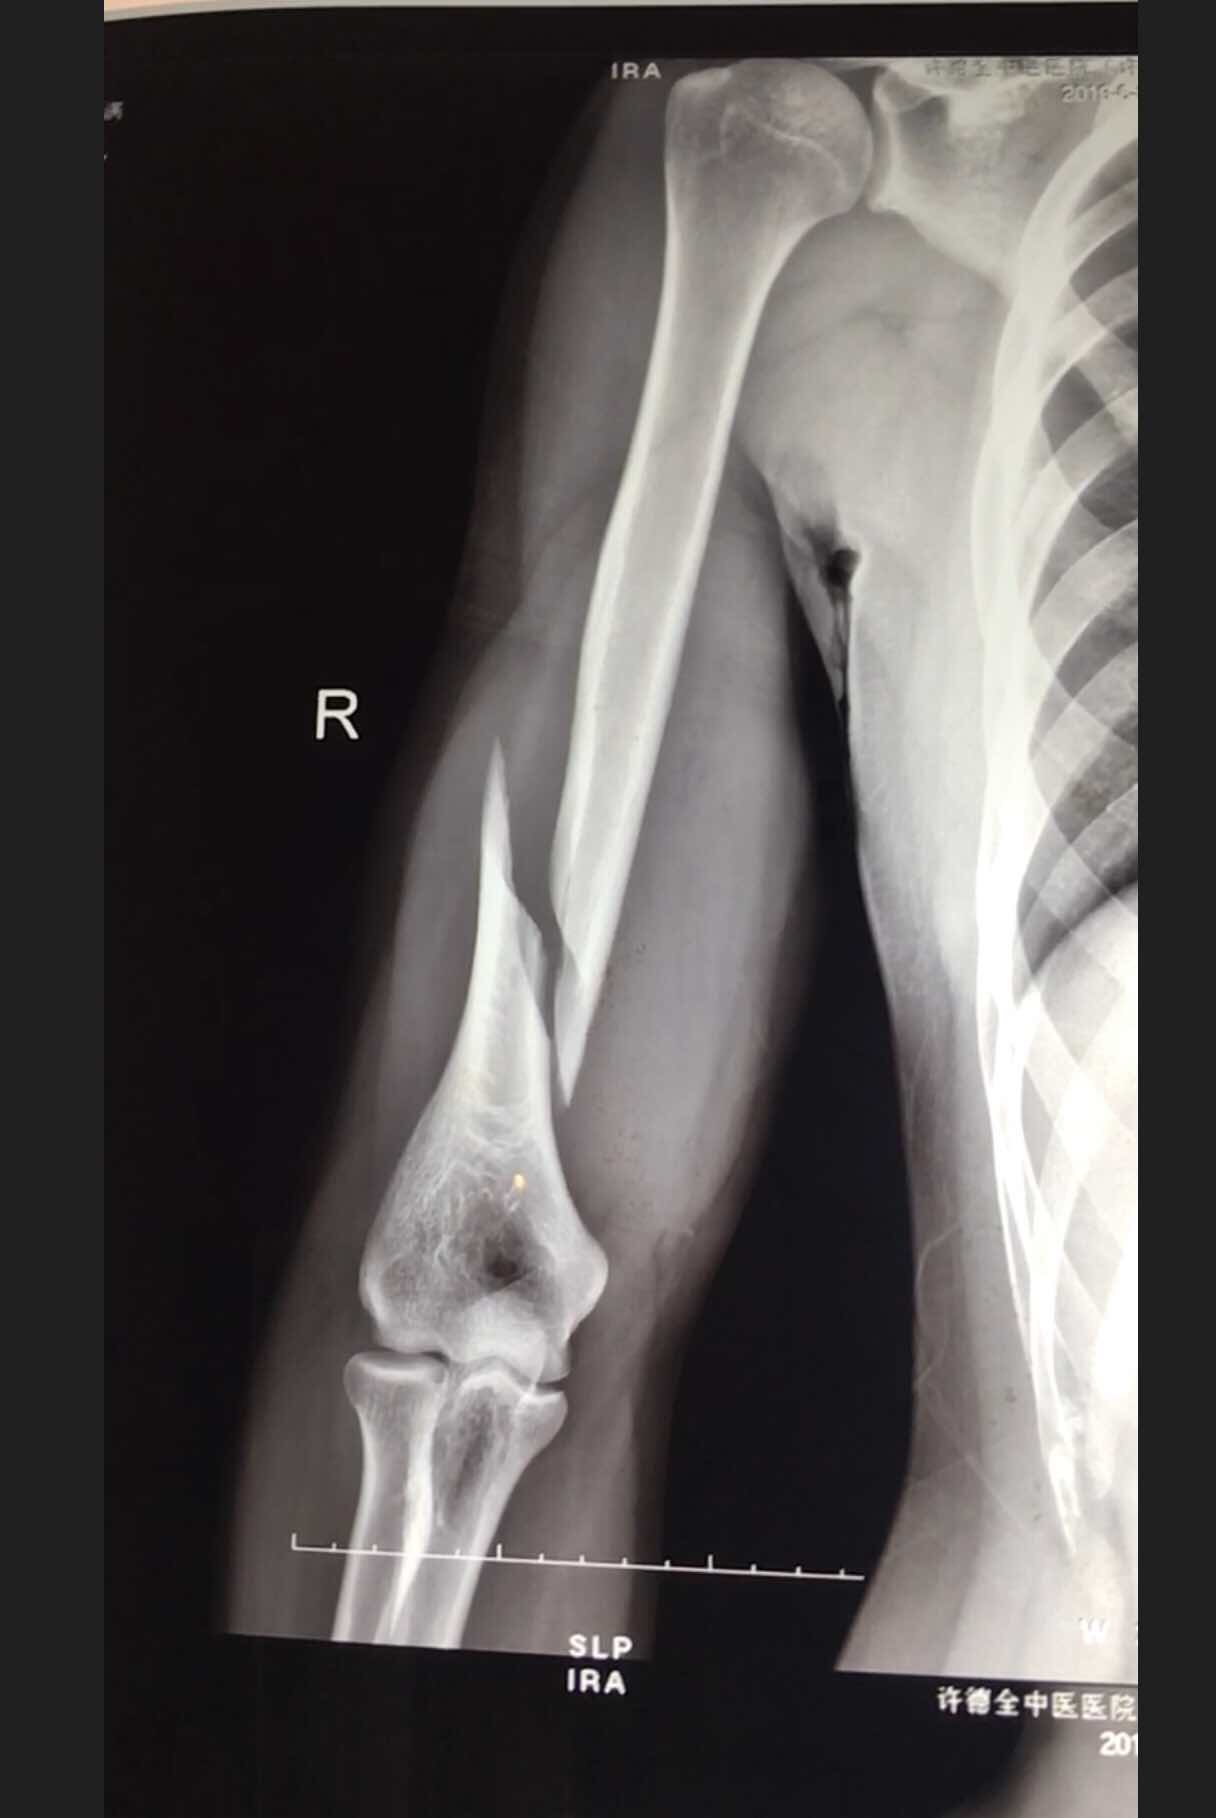

肱骨远端骨折(切复双钛板内固定)

摔伤后右肘部肿胀,畸形,活动受限2小时入院。既往身体健康,无特殊不良嗜好。从事健身教练工作数年。

生命体征平稳,心肺复未见异常。右上臂肿胀明显,畸形,局部皮色发红,皮温高,压痛及纵叩痛阳性,可及骨檫音及骨檫感,异常活动,末梢血运感觉正常。

诊断肱骨远端骨折在臂丛麻醉下行切复内固定术,术后抗炎,消肿等处理。